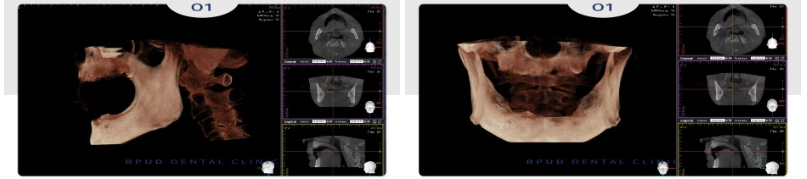

전체적인 수복을 원하셨기 때문에

3D CT를 통한 면밀한 진단을 통해

위쪽 12개, 아래쪽 9개의 임플란트를

수복하기로 계획을 수립하였는데요.

아래쪽은 신경의 위치를 고려하여

작은 어금니 부위는 인공치아로 대체하였고

오랜 기간 틀니의 사용으로

전체적으로 많이 흡수가 진행된

잇몸뼈는 치조골 이식을 통해

회복하기로 하였습니다.

환자분과 같이 치조골이 부족한 경우라면

뼈이식이나 상악동 거상술을 병행해야 하는

경우가 있어 부평치과 전체임플란트는

난이도가 높은 시술에 해당하는데요.

이 때문에 정밀 검진을 통해 잇몸뼈 상태를

파악하고 개인 맞춤형 치료 계획을

수립하는 것이 가장 중요합니다.

최근에는 3D CT 등 디지털 장비를 통해

안정적으로 편안한 진행이 가능합니다.